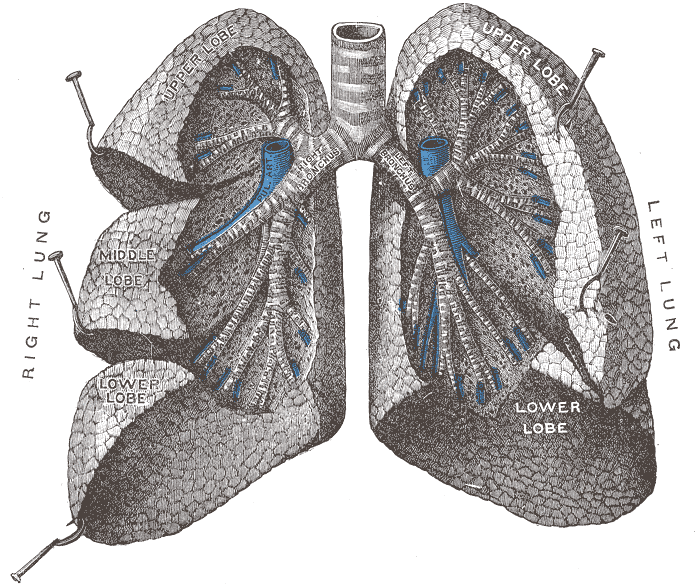

- Figure 1. Lung anatomy53

- The trachea branches into the two primary bronchi at the hilum, which then divide into bronchioles. These subsequently branch off into the alveolar ducts and then the alveoli themselves.

- Each lung is enclosed within visceral pleura, dividing the right lung into three lobes and the left lung into two. These structures all lie within the parietal pleura adherent to the inner wall of the rib cage. The pleural cavity in between these two layers contains a lubricating pleural fluid.